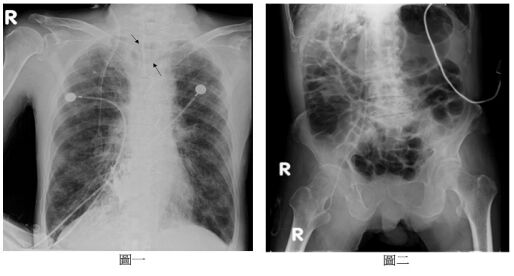

63.70歲COPD男病人,因呼吸衰竭長期倚賴呼吸器已半年,3天前因呼吸急促轉入加護病房,胸部及腹部X光如圖一和圖二,身體理學檢查發現腹脹,胃部聽診有氣流流動聲且和呼吸器吸氣期同步,病人最可能發生下列何者診斷?(A)食道插管 (B)氣囊漏氣 (C)氣管食道瘻管 (D)單肺插管